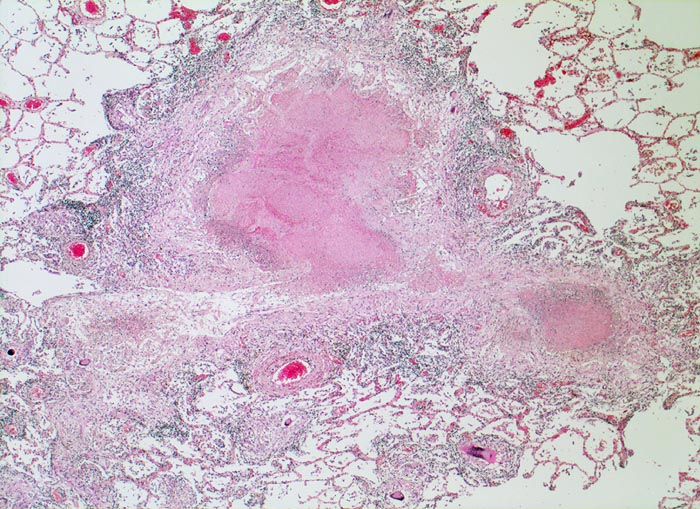

Das morphologische Bild ist äusserst variabel. Je nach Abwehrlage, Art und Geschwindigkeit der Ausbreitung entstehen unterschiedlich grosse, teils geschichtete Herde mit unterschiedlichem Grad an Epitheloidzellreaktion, zentraler Nekrose bzw. Vernarbung. Rein produktive Granulome ohne Nekrosen sind Zeichen guter Abwehrlage. Der Begriff Verkäsung bezieht sich auf den makroskopischen Aspekt von Nekrosen, der an Frischkäse erinnert. Exsudative nekrotisierende Granulome entstehen bevorzugt bei schlechter Abwehrlage. In späteren Stadien der Lungentuberkulose unterscheidet man produktive Phthisen mit azinös nodösen Gruppen von bronchogen entstandenen gering verkäsenden Streuherden (Präparat), zirrhotische Phthisen mit gering verkäsenden stark vernarbenden Herden und exsudative Phthisen bei schlechter Abwehrlage. Bei letzterer steht die Verkäsung im Vordergrund. Die bakterienreichen Herde entstehen teils hämatogen, teils bronchogen. Verkäsende Herde sind Ausgangspunkt für die Kavernenbildung. Kavernen stellen die wichtigste Quelle für die bronchogene Streuung dar.

• Tuberkulöse Herde ausgehend von vollständig oder partiell entzündlich zerstörten Bronchiolen in unmittelbarer Nachbarschaft von Arterien.

• Granulome mit zentraler käsiger Nekrose mit Kerntrümmern umgeben von einem Epitheloidzellwall und einem äusseren blauen Saum von Lymphozyten.

• Schlanke spindelige Epitheloidzellen und einzelne Riesenzellen vom Langhanstyp mit peripher hufeisenförmig angeordneten Kernen.